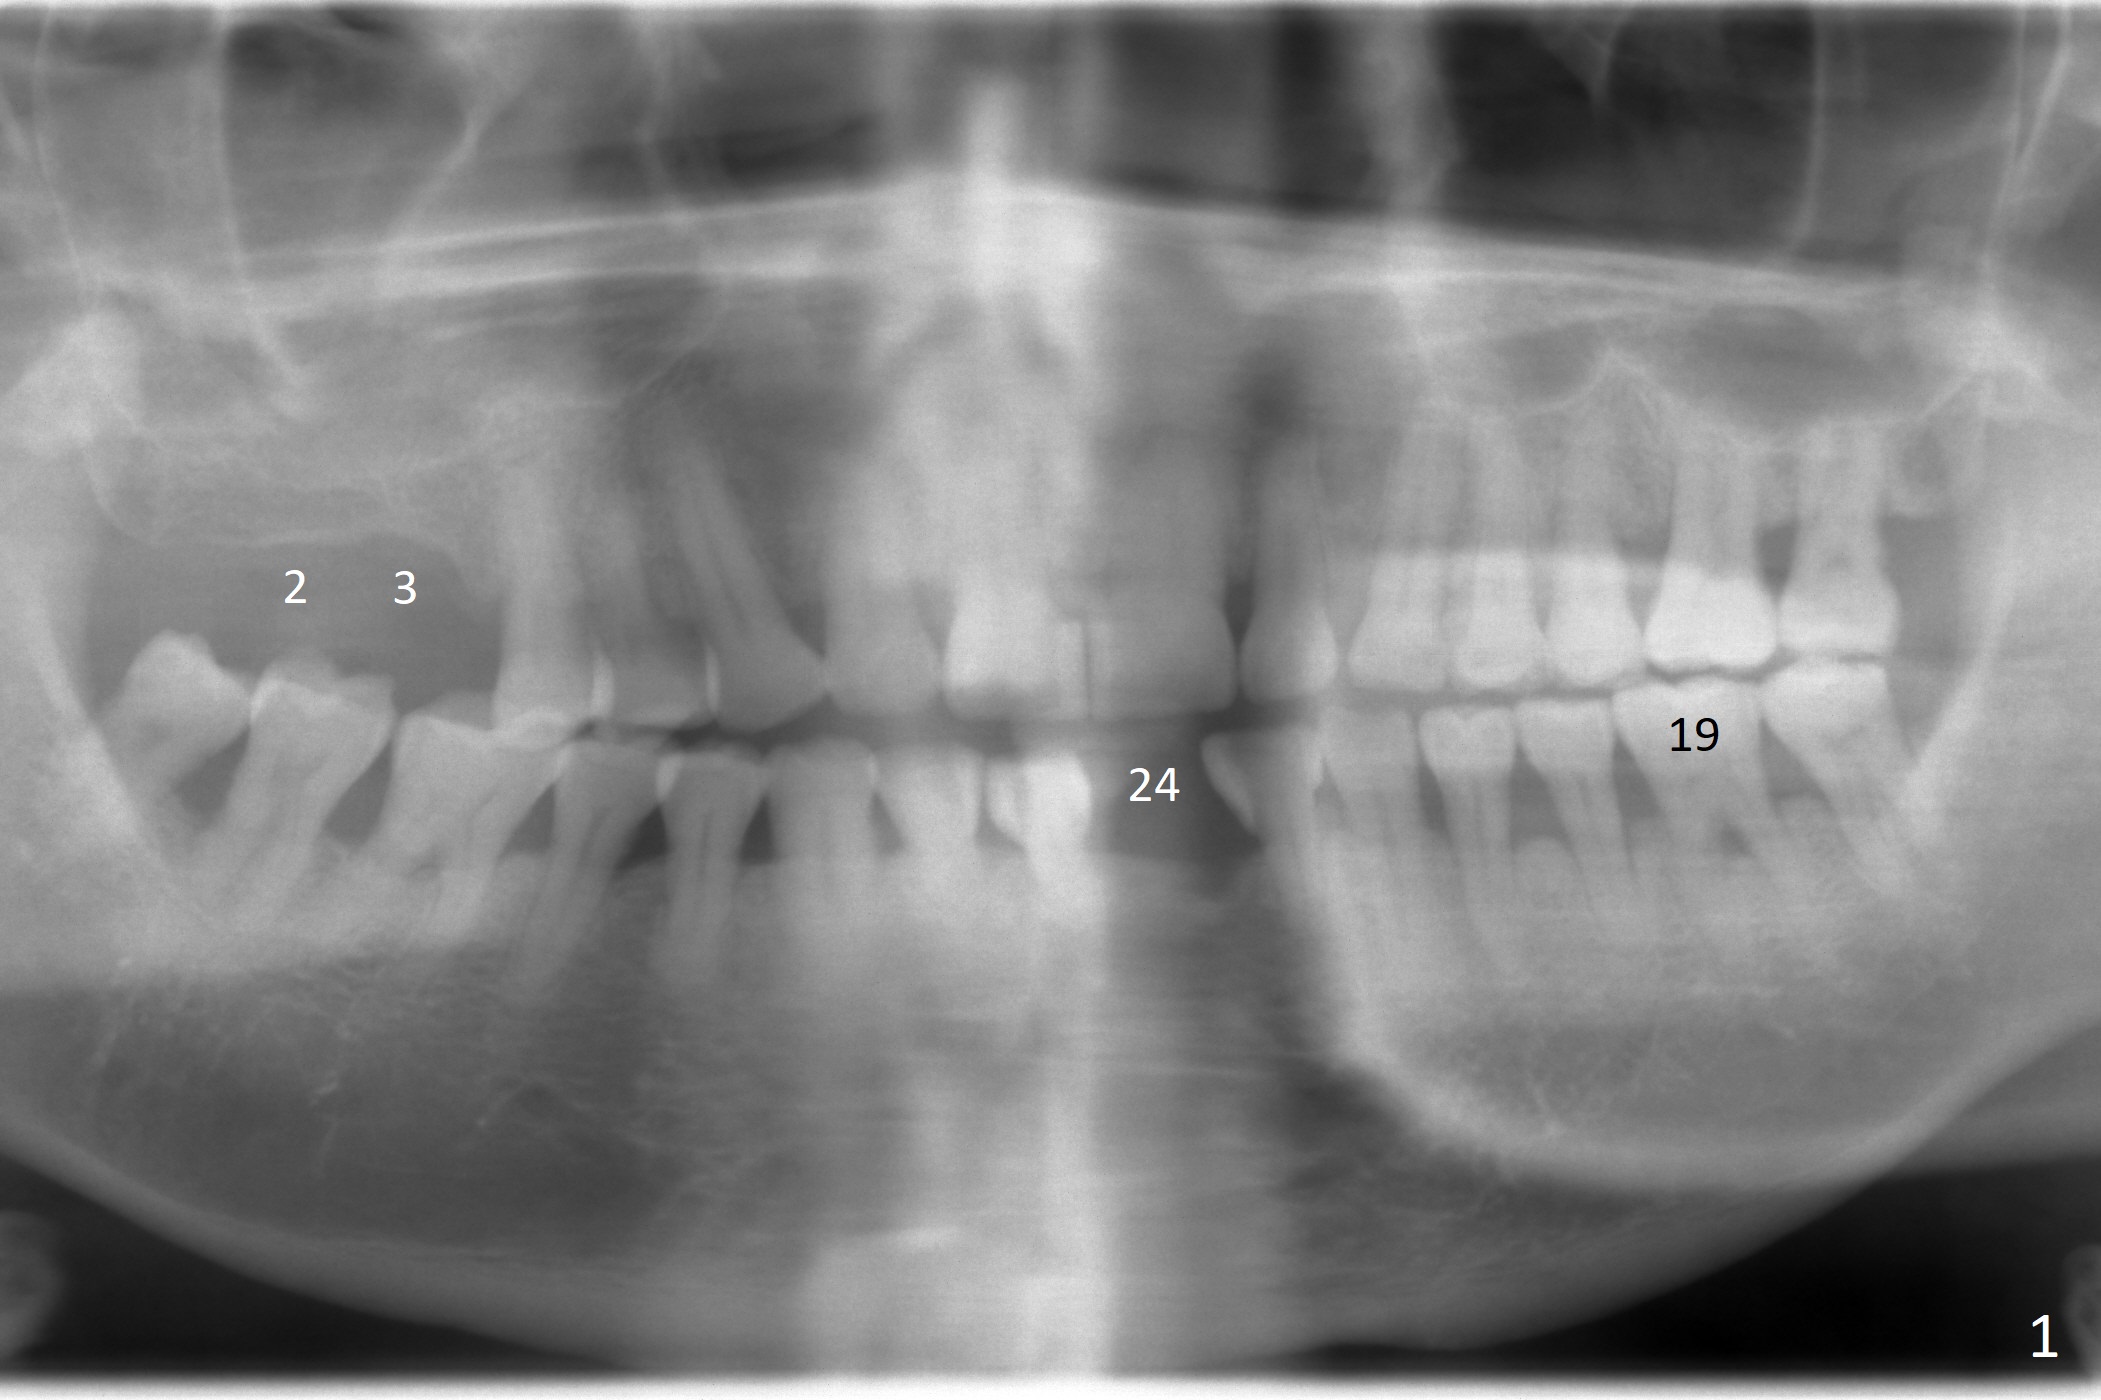

A 63-year-old man is a diabetic with history of good control. He masticates unilaterally with missing teeth #2,3 and 24 (Fig.1 (taken 5 years ago)). The latter has been restored with an implant. Last February the mesial root of the tooth #19 was found to have vertical fracture with bone loss until the base of the septum (Fig.2). The bone available for implantation is ~7-8 mm after root fracture (Fig.3,4). The initial osteotomy depth will be 7 mm (IS kit), followed by the calibrated parallel pin. The latter determines how many millimeters of an implant will be surrounded by the graft bone (Fig.4,5 (green: implant length; pink: cuff; blue: abutment length)). Since the buccal defect is severe with mesial root split (Fig.7 *), draw blood for PRF (2 large tubes). To save the remaining septum, place 2 of 1-piece implants on the either side of the septum (compare Fig.6,8). Take photos to compare buccal vs. lingual gingival recession. Tell the patient that the tooth #20 may be nonsalvageable. Since insurance preauthorization does not get approval for several times, the tooth #19 is extracted with socket preservation and periodontal dressing. The latter dislodges in 1 day. When the patient returns for follow up 4 days postop, the socket is exposed (Fig.9). An immediate implant should have been placed to keep the graft in place. PRF also helps. In fact preauthorization letter arrived 1 day earlier. It appears that guided surgery is indicated for limited bone height. The bone graft appears to gain ~ 5 mm bone in 4 months (Fig.10), which allows to place a 5x8.5 mm implant (Fig.11).